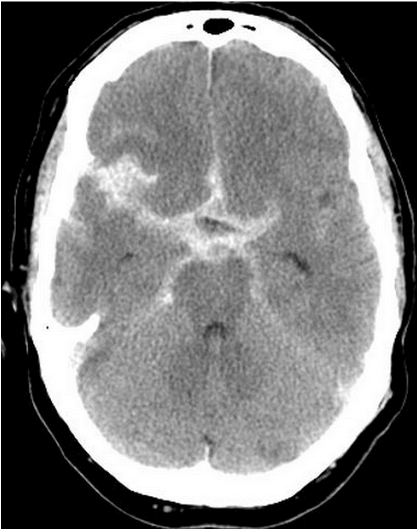

Subarachnoid hemorrhage is often due to rupture of a brain aneurysm. It is typically described as the patient’s “worst headache” and its onset is likened to a thunderclap.